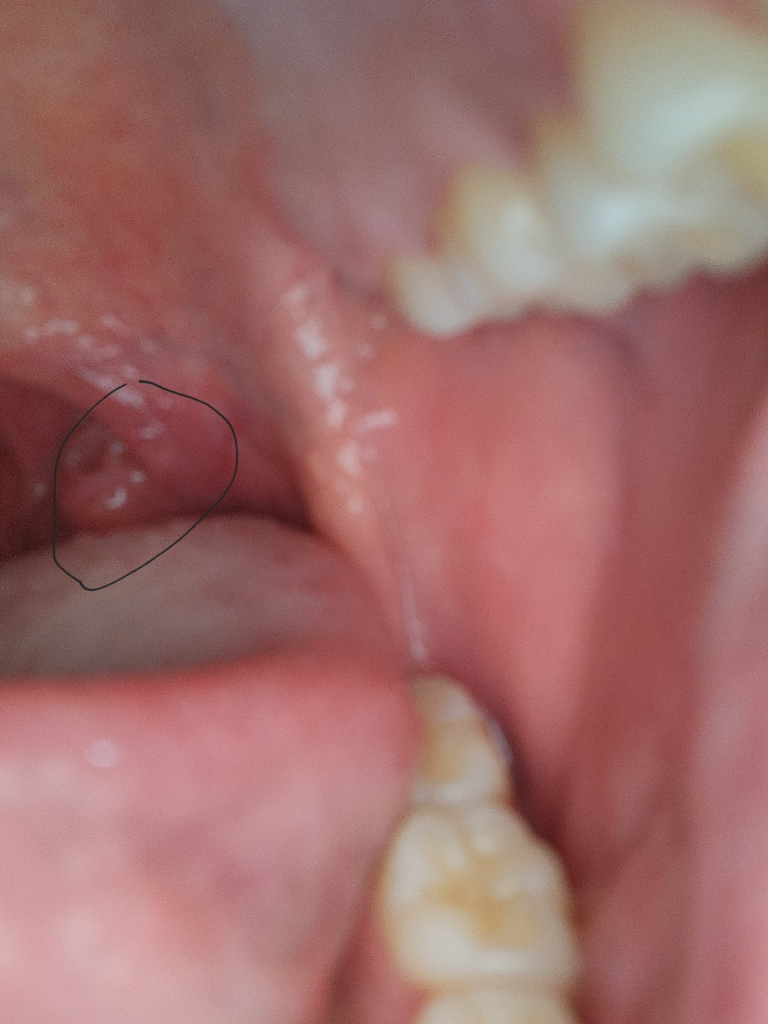

동그라미안에 있는것은 편도입니다. 편도가부어있고 구강점막이 건조해 보입니다. 수분섭취를 많이 하시고 염증약을 복용하면 도움이될것입니다.

정상적인 편도를 표시하신 것이라 보입니다. 가까운 이비인후과를 방문하시면 비정상적인 구조물이 존재하는지 더 명확히 진찰받아보실 수 있습니다.

해당 사진을 통해서는 구체적으로 파악하기는 어려워 보입니다. 사진을 통해서 보았을 때는 편도 같아 보이는 구조물이기도 합니다.